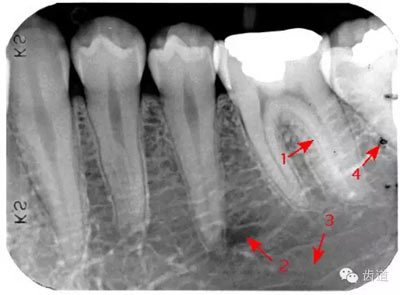

是機(jī)體中鈣化最高和最堅(jiān)硬的組織,X線片上的影像密度也最高,似帽狀被覆在牙冠部牙本質(zhì)的表面。后牙頜面、前牙切緣最厚,由頜面和切緣向側(cè)方至牙頸部逐漸變薄,終止于牙頸部。

圍繞牙髓構(gòu)成牙的主體,牙本質(zhì)中礦物質(zhì)的含量比釉質(zhì)少,X線影像的密度較牙釉質(zhì)稍低。

被覆在牙根表面,為一層很薄的組織,密度與牙本質(zhì)相當(dāng) 。

髓腔可分為冠部的髓室和根部的根管。牙髓內(nèi)含牙髓軟組織,X線片上顯示為密度低的影像。年輕人的牙、牙根未完全形成時(shí),根尖孔粗大,牙髓腔大。隨著年齡的增長(zhǎng),牙本質(zhì)逐漸增多,髓腔愈狹窄,根尖逐漸變細(xì)。

即固有牙槽骨,是牙槽骨的內(nèi)壁,圍繞牙根,骨質(zhì)致密而薄,X線片上顯示為包繞牙根的連續(xù)不斷的密度高的線條狀影像。

是介于牙槽窩和牙骨質(zhì)之間的結(jié)締組織。牙周膜的厚度一般在0.15~0.38mm之間。X線上顯示為包繞牙根連續(xù)不斷的密度低的線條狀影像,其寬度均勻一致